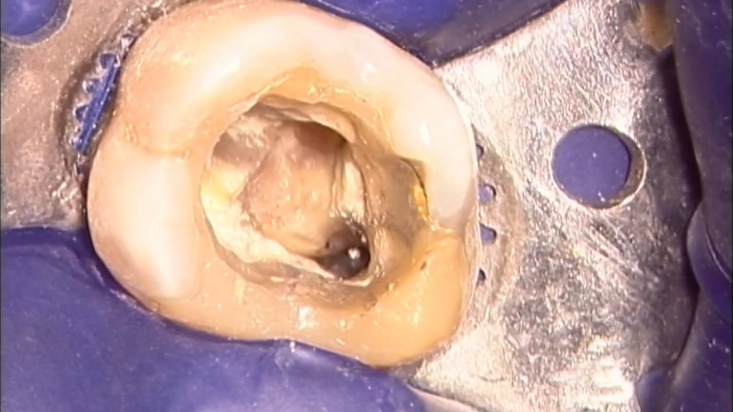

Сл. 37.79

Сл. 37.79 а) Предоперативна радиографија на ендодонтски неуспех кај лев прв молар. Забот има колче со навој во палатиналниот канал и скршен инструмент во мезиобукалниот канал. б) По отстранувањето на колчето за навој и чистењето на пулпината комора, најкоронарниот дел од рагментот сега е евидентен под оперативниот микроскоп. в) „Проултра“ #4 го изолира фрагментот и пренесува вибрации, додека стоматолошкиот асистент дува воздух со помош на Стропко иригаторот. г) Сега фрагментот е поочигледен. д) Фрагментот е отстранет со ултразвук и сега е на кофердамот, во близина на стегачот на кофердамот. ѓ, е) Клиничката слика и филмот го потврдуваат отстранувањето на фрагментот. ж) Постоперативен филм.